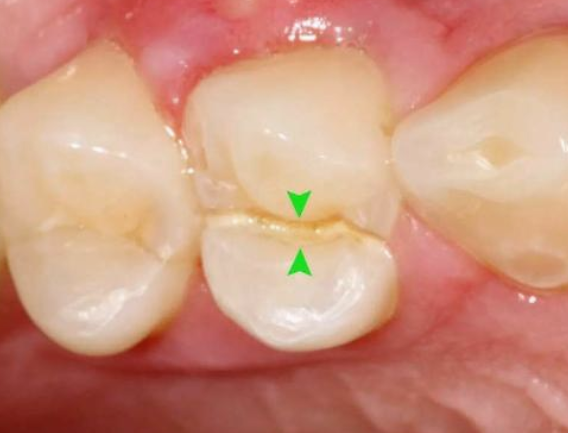

真实案例:下面这幅图片就是一个牙科医生发出来的一个患者的牙,之前做了“根管治疗”后,没有及时做“牙冠”,导致吃东西时把原来做过‘根管治疗’的牙直接劈成了2半,这不是既麻烦又难受?后悔都来不及了!!

因为需要进行根管治疗的牙齿,一般已经是蛀牙缺损很大,这个时候虽然根管治疗完成,但是剩下的牙体组织脆弱,容易折断、裂开,失去正常的功能,单纯用材料已经没法恢复功能。

二:治疗后不太足够支持咀嚼的力量

根管治疗是以药物,以及器械的操作来将根管内的残渣,以及细菌尽可能地清除消毒干净。然而,这样的消毒过程如果要认真的进行,却去除掉不少被细菌感染的牙齿,以及不得不修正的牙体组织。所以大部分的牙齿一旦进行根管治疗,则可能不太足够支持咀嚼的力量而可能断裂。

三:失去了来自牙髓的营养供应

经过根管治疗后的牙齿失去了来自牙髓的营养供应,就像失去树根的树木一样,慢慢枯萎变的很脆弱,造成牙齿的脆性增加,易劈裂。

所以,不是医生想多赚你的钱,是因为杀掉神经的牙齿是真的脆弱,而这时候做一个“牙冠”的目的是保护了这颗“脆弱的牙齿”,避免牙齿再次“损伤”。